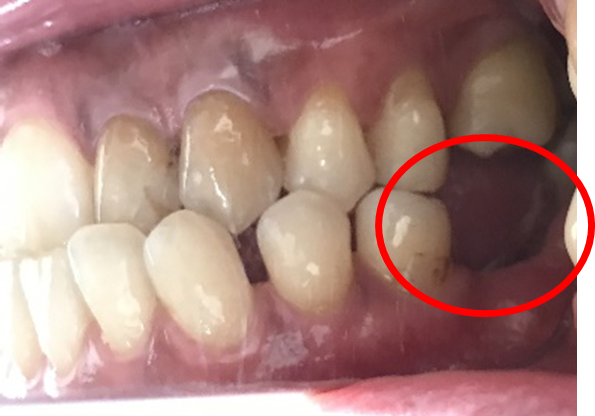

Before

冠の中で大きな虫歯になり支台の役割を果たしていませんでした。

【インプラント埋入前】

冠はブリッジを切断しただけで取れてきました。軟化象牙質を取り除いたところ、歯根しか残っていない状況で保存できるかどうかのぎりぎりのところでした。